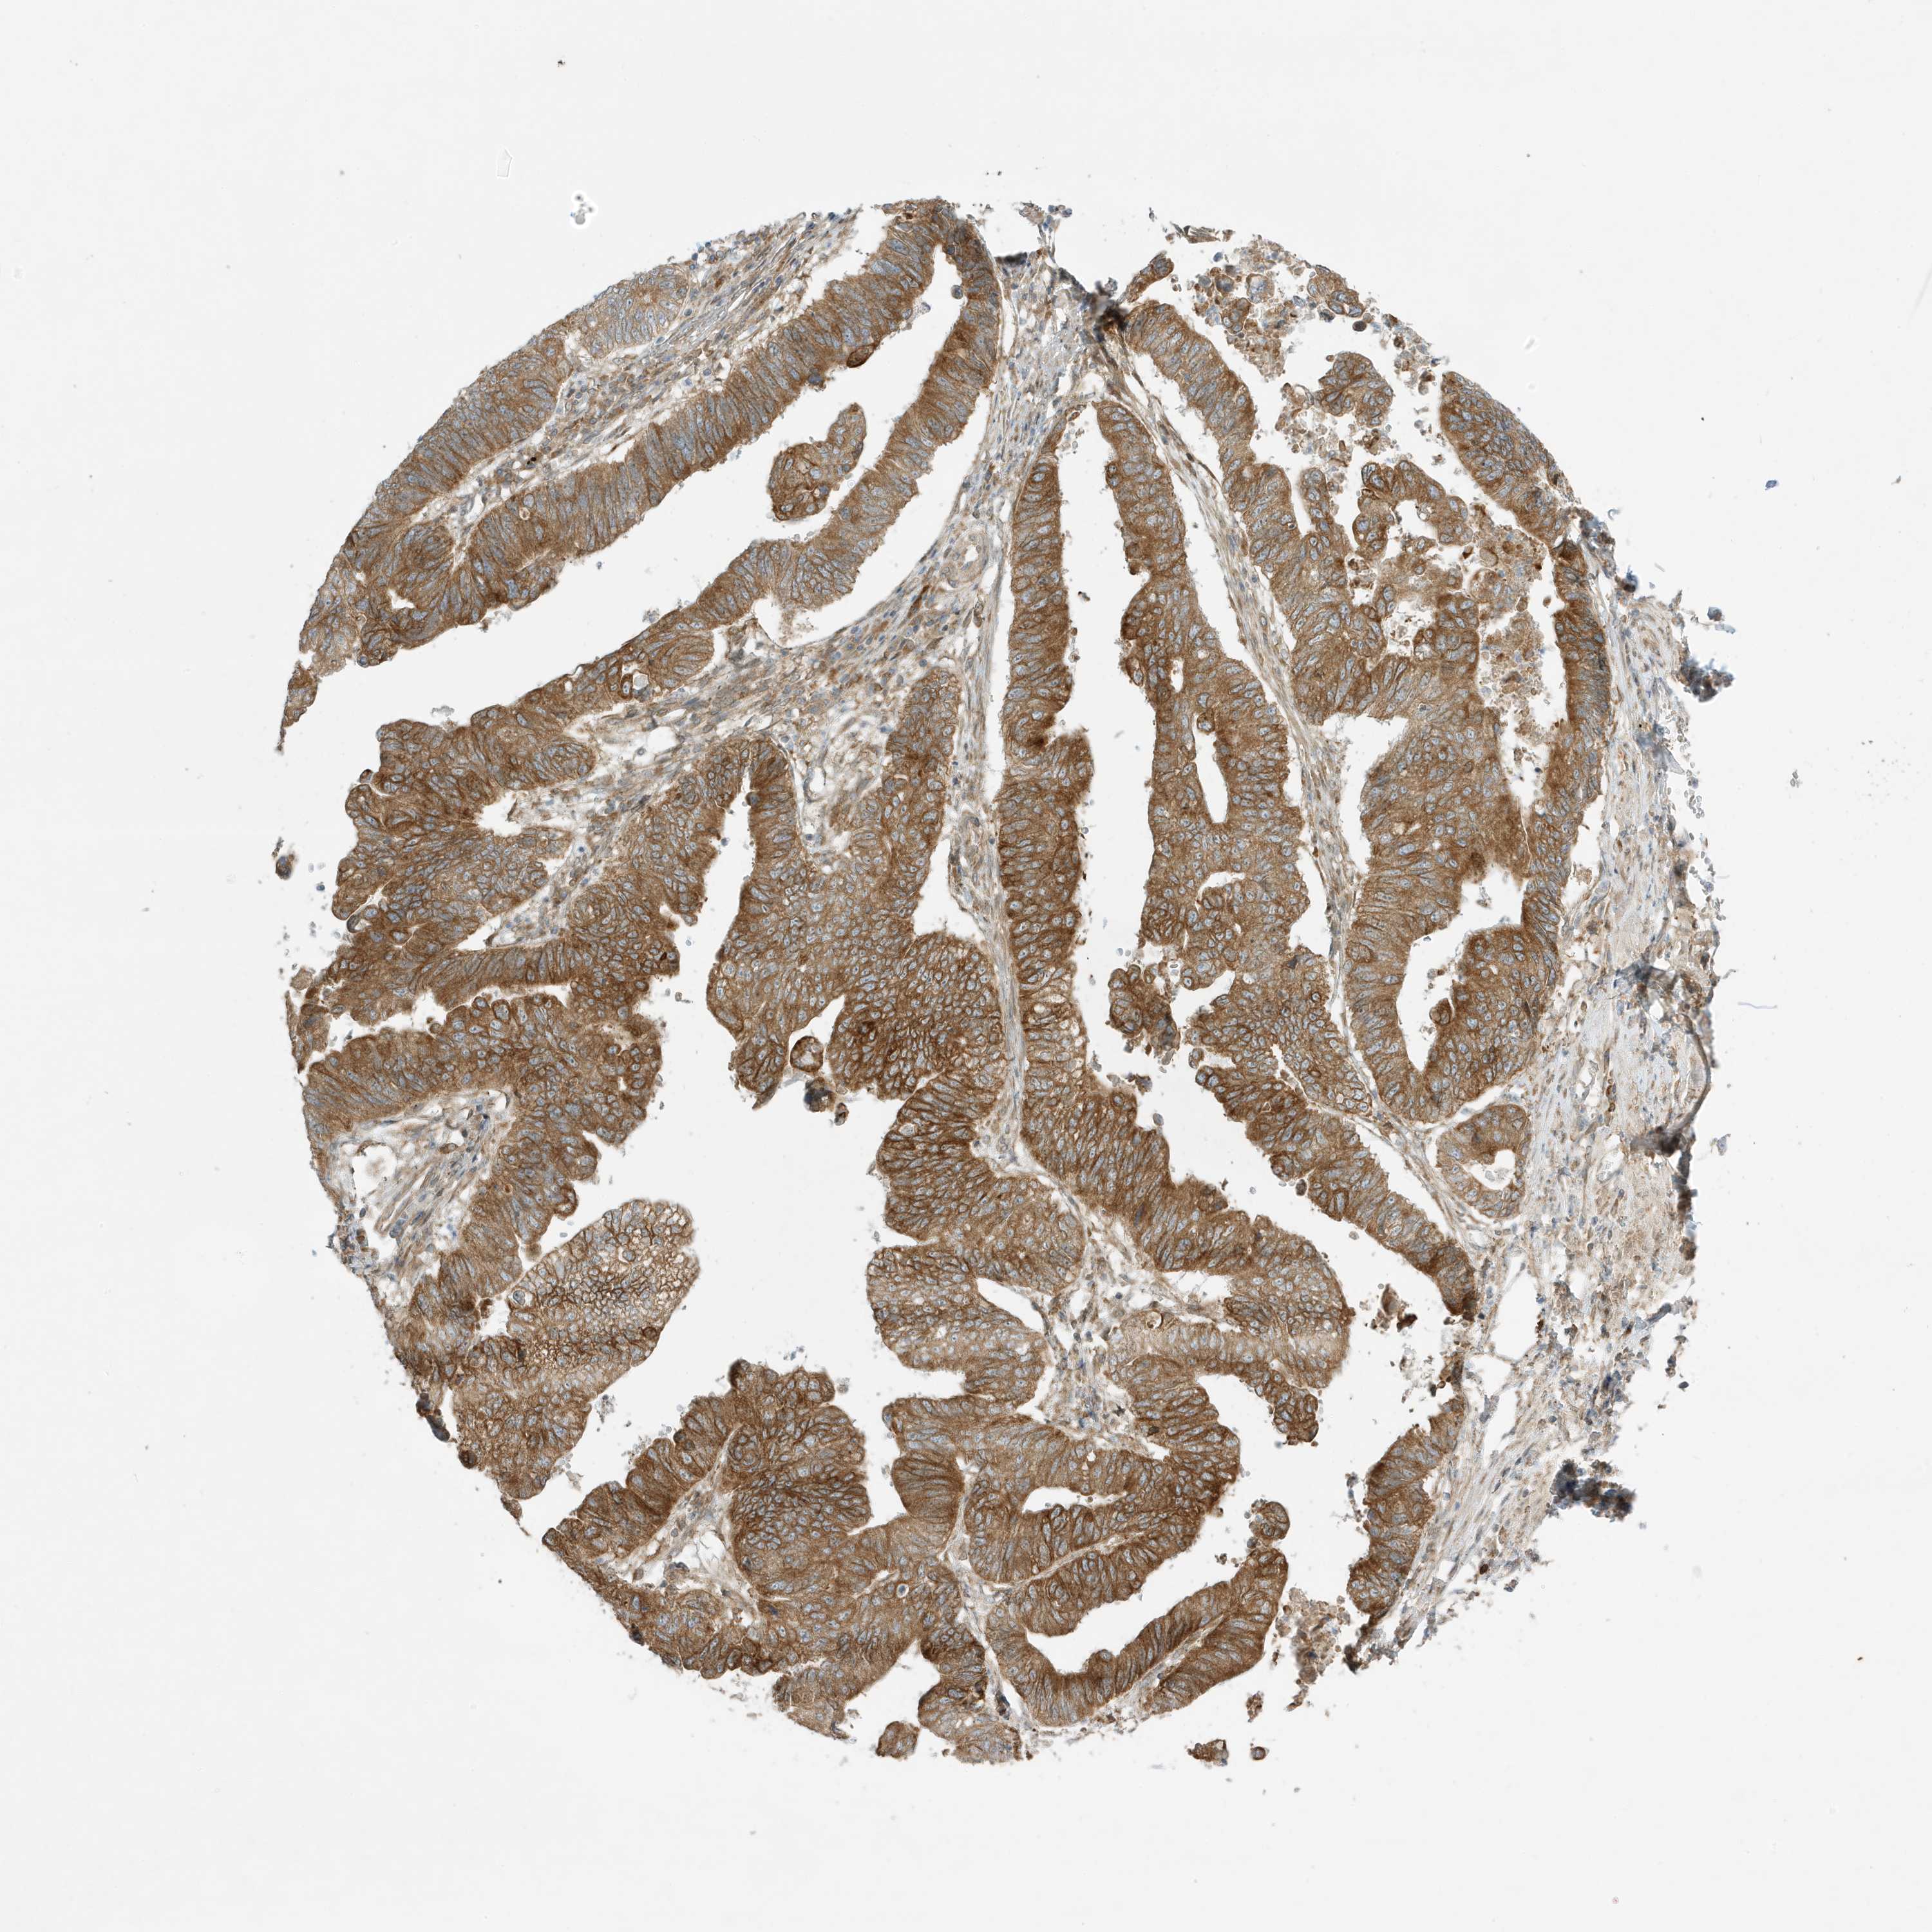

STOMACH CANCER - Protein expressioni

A mouse-over function shows sample information and annotation data. Click on an image to view it in a full screen mode. Samples can be filtered based on level of antibody staining by selecting one or several of the following categories: high, medium, low and not detected. The assay and annotation is described here.

Antibody stainingi

Antibody staining in the annotated cell types in the current human tissue is reported as not detected, low, medium, or high, based on conventional immunohistochemistry profiling in selected tissues. This score is based on the combination of the staining intensity and fraction of stained cells.

Each image is clickable and will lead to virtual microscopy that enables deeper exploration of all samples and also displays staining intensity scores, fraction scores and subcellular localization as well as patient and tissue information for each sample.

Antibody HPA035079

Staining

High

Medium

Low

Not detected

Intensity

Strong

Moderate

Weak

Negative

Quantity

>75%

75%-25%

<25%

None

Location

Nuclear

Cytoplasmic/membranous

Cytoplasmic/membranous,nuclear

Adenocarcinoma, NOS